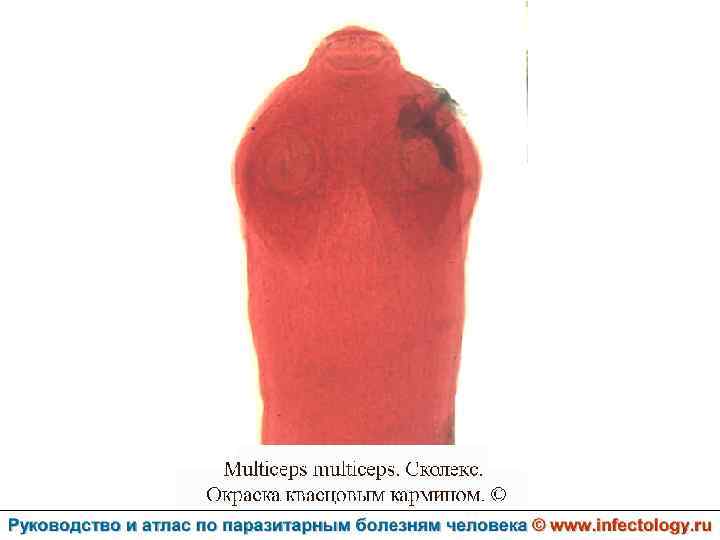

Ценуроз (шифр по МКБ 10 – B 71. 8)– спорадически встречающееся заболевание человека, вызываемое личиночной формой (ценуром) гельминтов рода Multiceps, половозрелые формы которых паразитируют у собак и диких волчьих. . Проявляется разнообразными клиническими симптомами в зависимости от вида паразита.